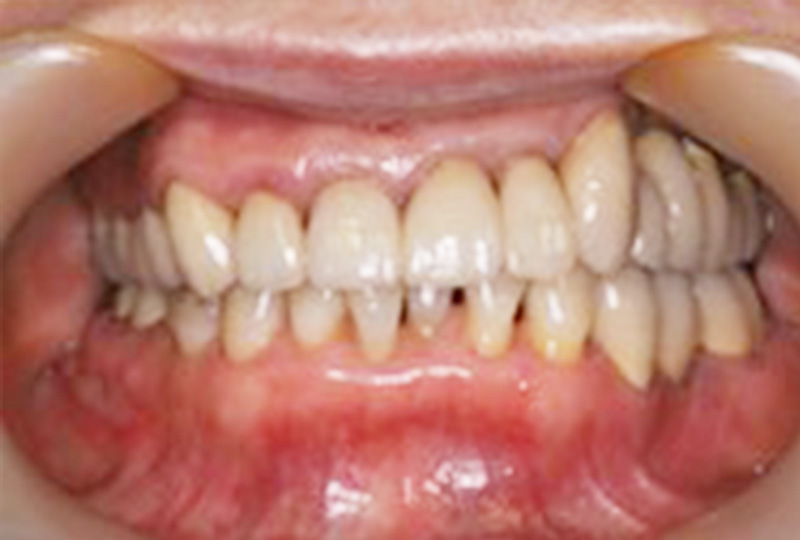

審美性にこだわった治療から保存が難しいと言われた歯の保存やお口全体をより良い状態にする一歩進んだ専門的な治療を行います。

『歯のひび(歯根破折)』など通常であれば抜歯と言われるような歯の保存や歯を失った所に親知らずなどを移動させる『歯の移植』など一般の歯科医院では行わない特殊な治療も行なっております。